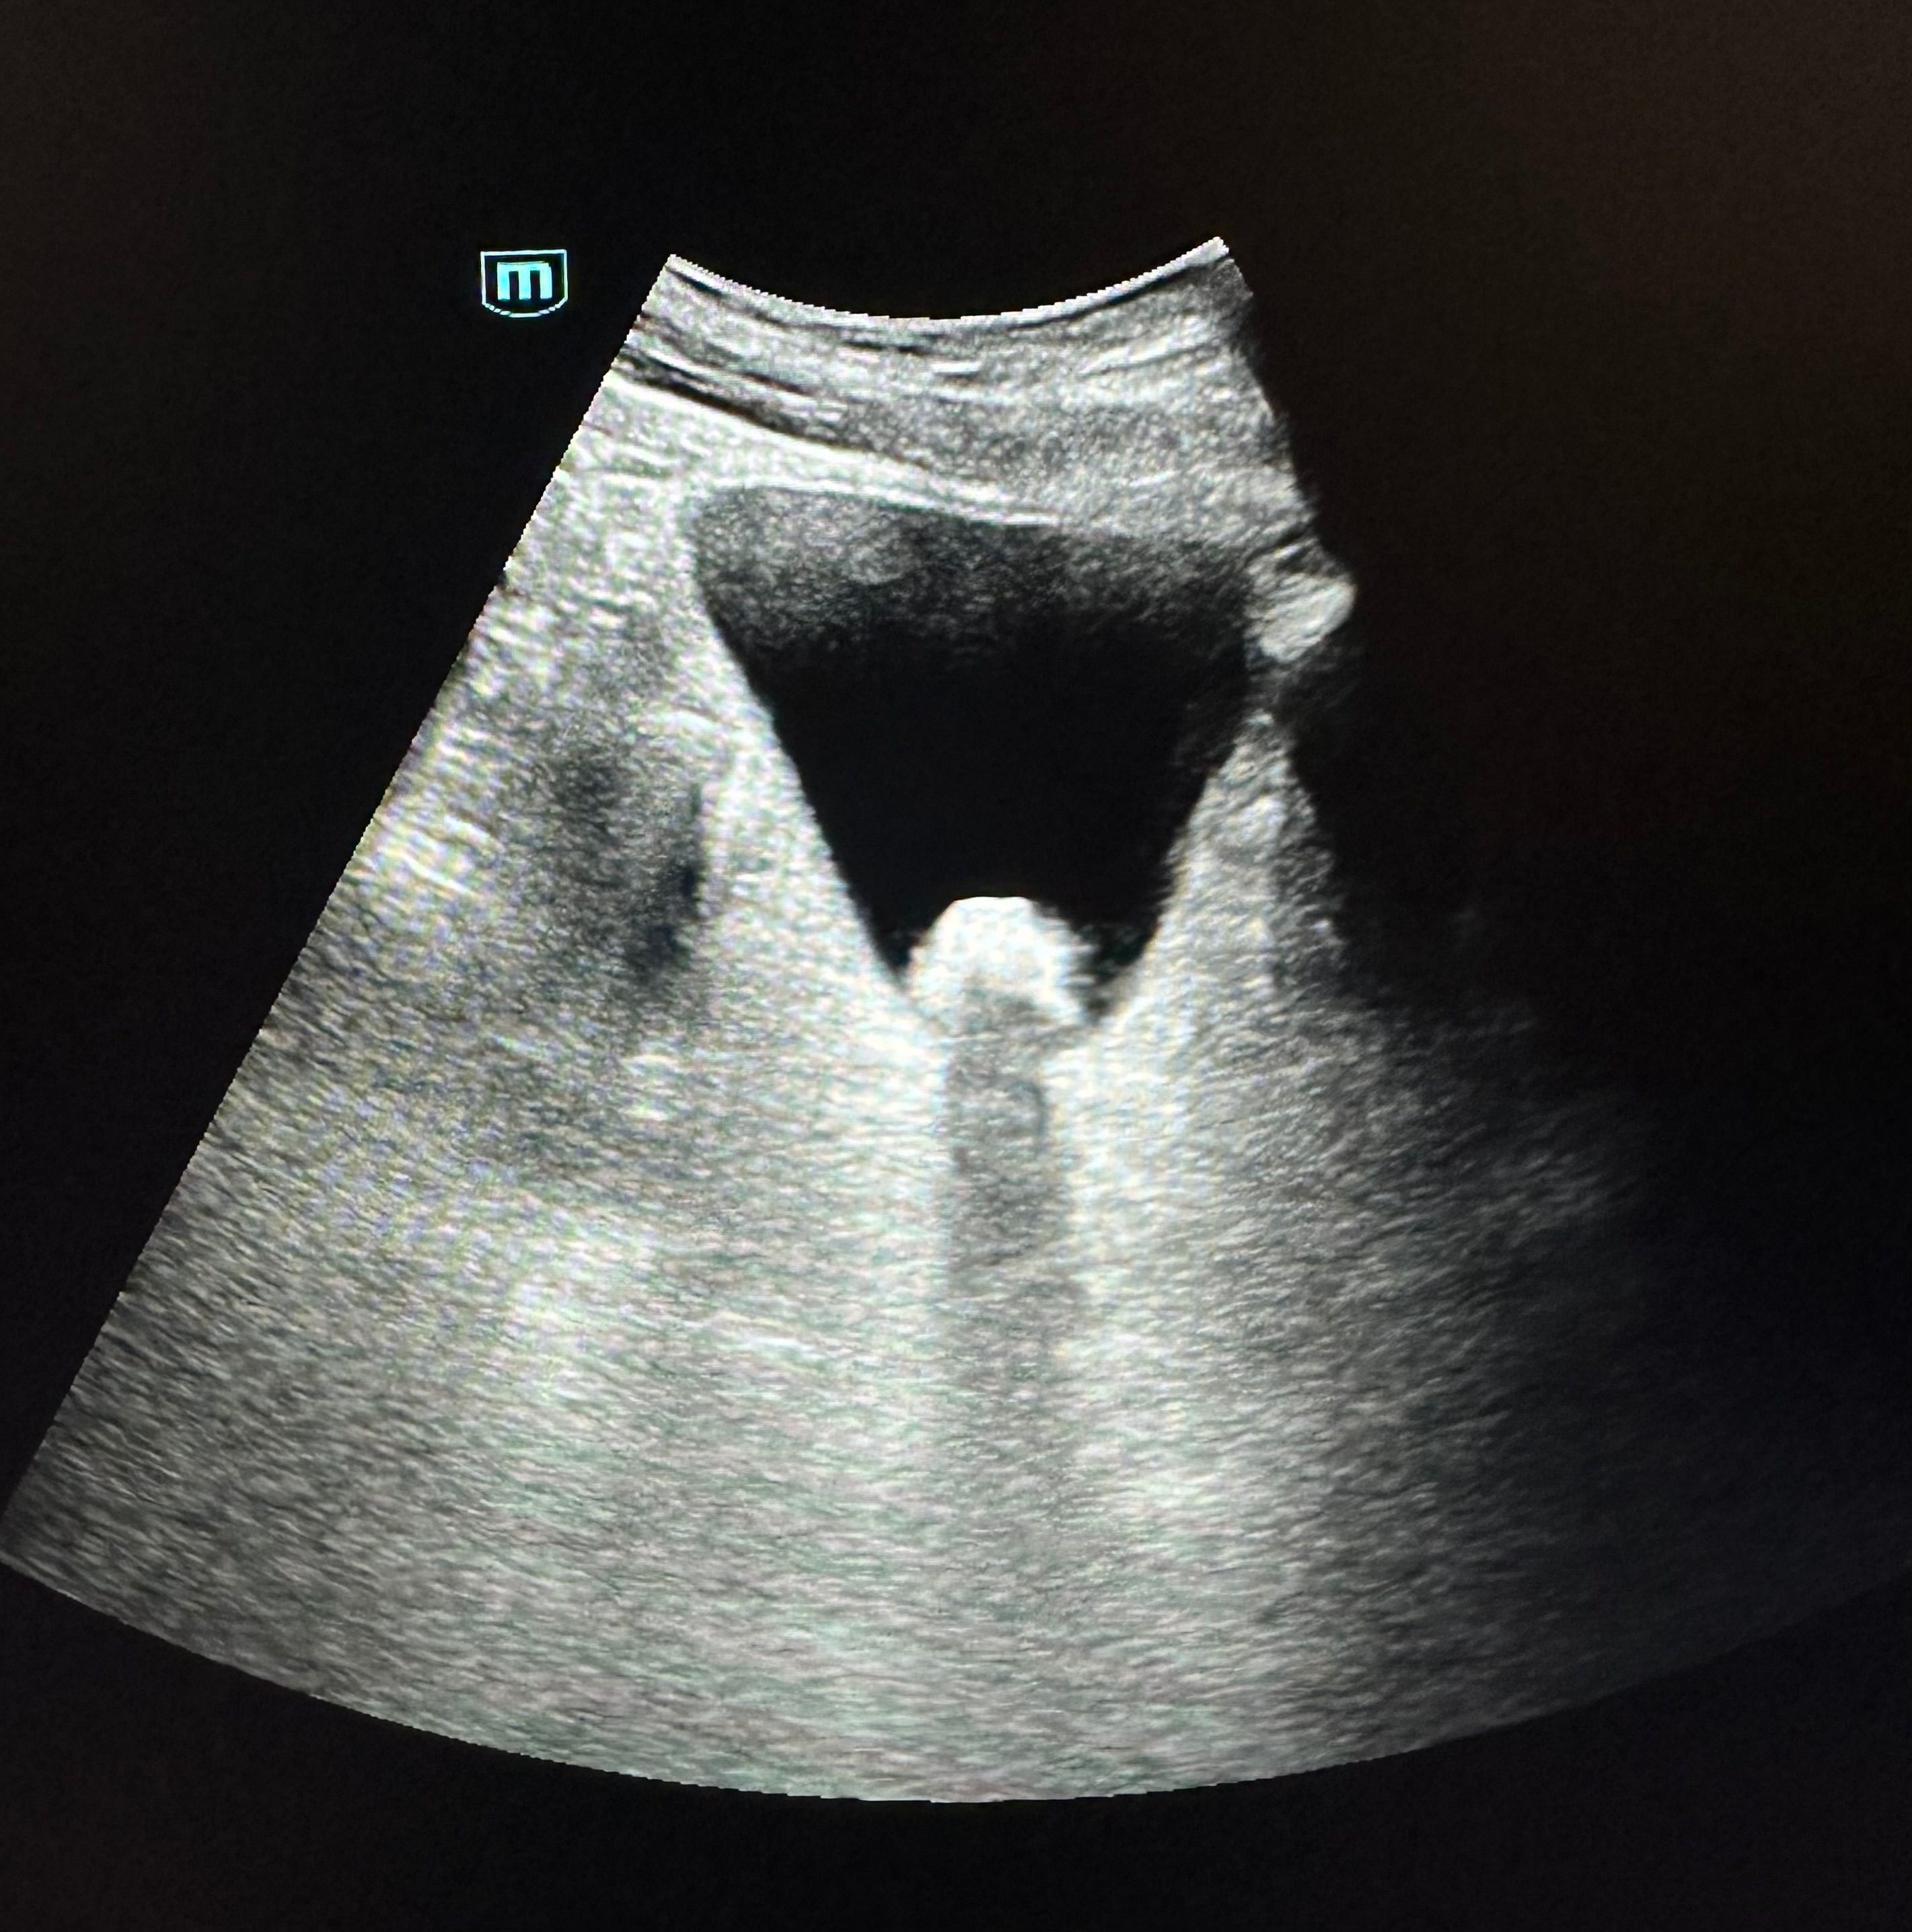

Hallazgos ecográficos

En la ecografía realizada se observó una litiasis vesical de 1,6 cm x 1,5 cm. No se observó dilatación de la vía urinaria ni otros hallazgos relevantes que sugirieran complicaciones agudas.